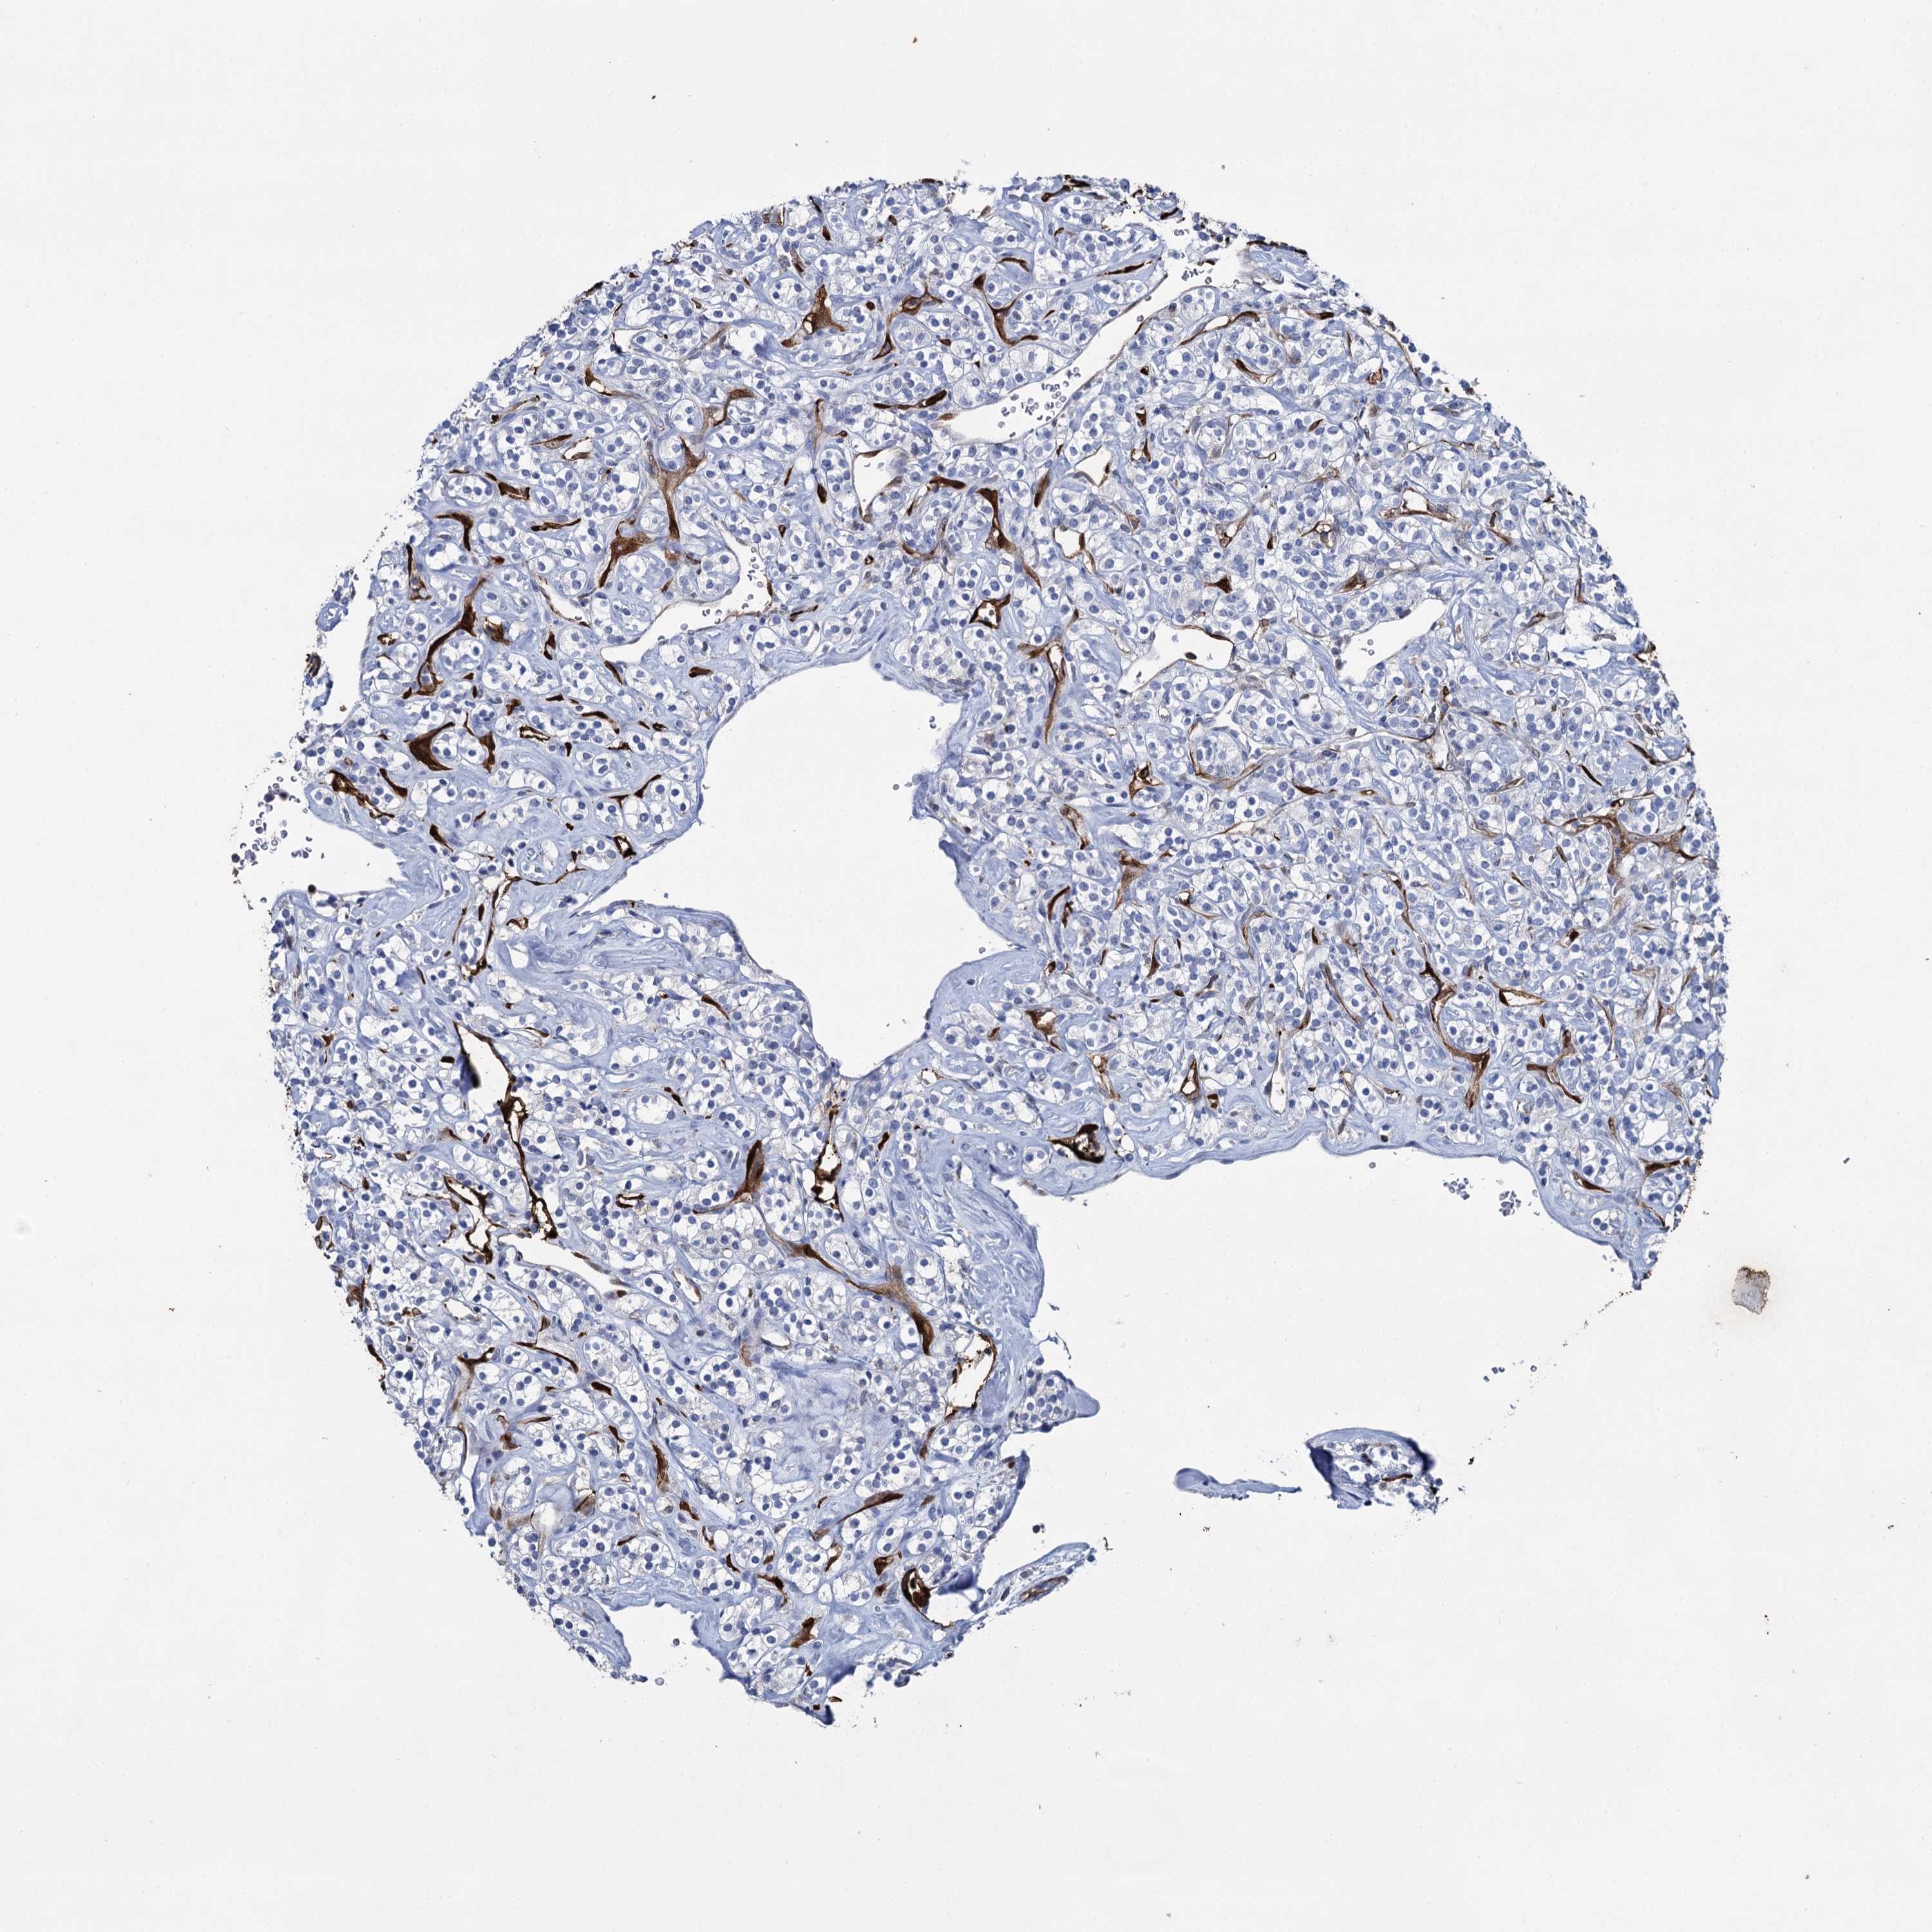

Renal cancer

Kidney renal clear cell carcinoma

KIDNEY RENAL CLEAR CELL CARCINOMA (TCGA) - Interactive survival scatter ploti

The Survival Scatter plot shows the clinical status (i.e. dead or alive) for all individuals in the patient cohort, based on the same data that underlies the corresponding Kaplan-Meier plots. Patients that are alive at last time for follow-up are shown in blue and patients who have died during the study are shown in red.

The x-axis shows the expression levels (FPKM) of the investigated gene in the tumor tissue at the time of diagnosis. The y-axis shows the follow-up time after diagnosis (years). Both axes are complimented with kernel density curves demonstrating the data density over the axes. The top density plot shows the expression levels (FPKM) distribution among dead (red) and alive patients (blue). The right density plot shows the data density of the survived years of dead patients with high and low expression levels respectively, stratified using the cutoff indicated by the vertical dashed line through the Survival Scatter plot. This cutoff is automatically defined based on the FPKM cutoff that minimizes the p-score. The cutoff can be changed by dragging the vertical line or by entering a cutoff value in the square labeled "Current cut-off".

Under the Survival Scatter plot the p-score landscape (black curve; left axis) is shown together with dead median separation (red curve; right axis). Dead median separation is the difference in median mRNA expression between patients who have died with high and low expression, respectively. It is calculated as follows: median FPKM expression of dead patients with high expression - median FPKM expression of dead patients with low expression. This is intended to aid the user in visually exploring custom cutoffs and the associated p-scores and dead median separation.

Individual patient data is displayed and can be filtered by clicking on one or more of the category buttons on the top of the page. Categories describing expression level and patient information include: high, low, alive, dead, female, male and tumor stages. The scale of the x-axis can be toggled between linear and log-scale by clicking on the "x log" button. Mouse-over function shows TCGA ID, patient information and mRNA expression (FPKM) for each patient.

& Survival analysisi

Kaplan-Meier plots summarize results from analysis of correlation between mRNA expression level and patient survival. Patients were divided based on level of expression into one of the two groups "low" (under cut off) or "high" (over cut off). X-axis shows time for survival (years) and y-axis shows the probability of survival, where 1.0 corresponds to 100 percent.

FABP5 is validated prognostic, high expression is unfavorable in Kidney Renal Clear Cell Carcinoma (TCGA)

Best expression cut offi

: 105.35